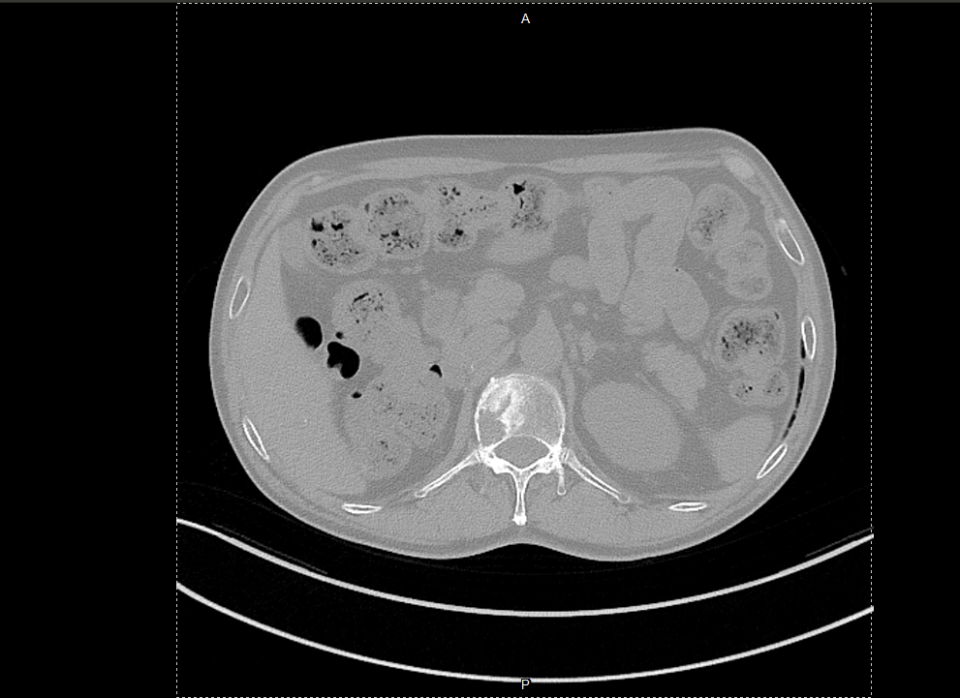

△2023年2月患者基线时CT(左)与2024年4月时CT(右)检查所见对比

△2025年8月疗效评估时患者CT检查(右)较基线(左)对比